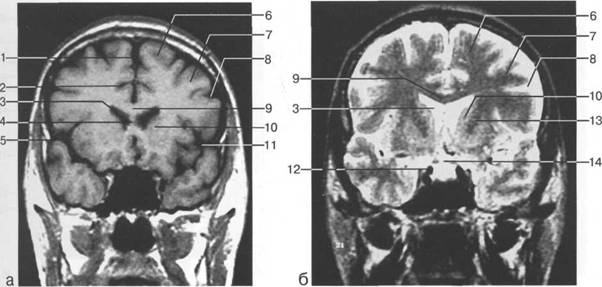

В латеральных отделах дно передней череп 13513u2010n 85;ой ямки образовано крышами глазниц, а в центральном - продырявленной пластинкой. Базальные отделы лобных долей представлены ко

ные извилины (рис. 1.10). Структуры средней череп 13513u2010n 85;ой ямки ограничены спереди малым крылом основной кости, снизу - большим крылом, сзади - передней поверхностью пирами «edge» «bone»

Содержимое средней череп 13513u2010n 85;ой ямки представлено базальными отделами височной доли.

ристый синус с внутренней сонной артерией, череп 13513u2010n 85;о-мозговые нервы) дифференцировать тральные отделы основания череп 13513u2010n 72; занимает турецкое седло. В полости турецкого седла ви

III ди зрительного бугра идет ретроталамическая цистерна, ориентированная во фронтальной

теменно-затылочная борозда; 11 - семиовальные